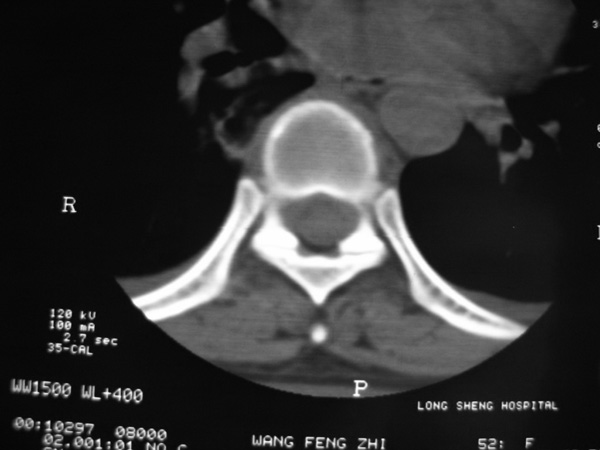

女,45岁,胸背部疼痛2个月。t6、7胸椎病变。

椎旁肿胀的软组织内可见气泡影,对脊柱的化脓性和结核性的鉴别有帮助吗?

胸椎结核伴冷脓肿形成且侵入椎管。

胸椎体骨质破坏伴死骨形成,椎周环状软组织肿胀,范围较长,考虑胸椎结核伴冷脓肿形成。鉴别;1转移性肿瘤;椎弓根骨质破坏多见,软组织肿块局限。椎间隙尚存。有原发肿瘤病史。2,淋巴瘤;骨质破坏 然骨皮质轮廓线尚存,当椎管骨示环状软组织影时有一定特异性。病变较局限。建议mri增强,观察冷脓肿与软组织肿块很有帮助。